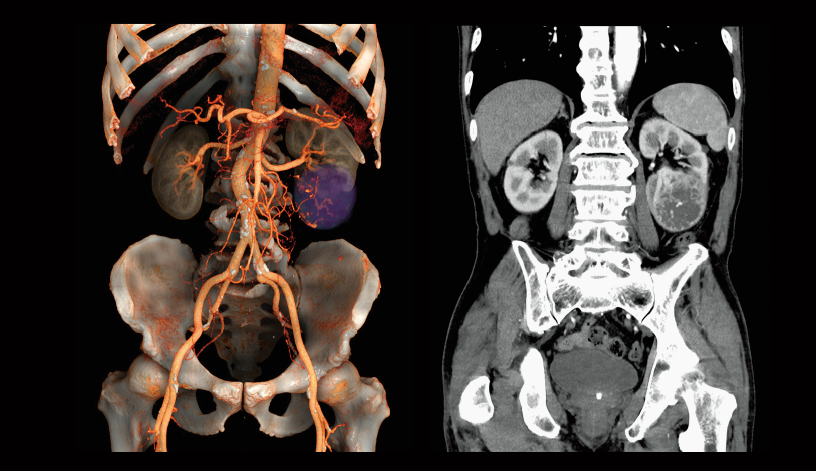

Desaturación intraoperatoria de oxígeno (izquierda)

Oclusión de la arteria ilíaca común izquierda (derecha)